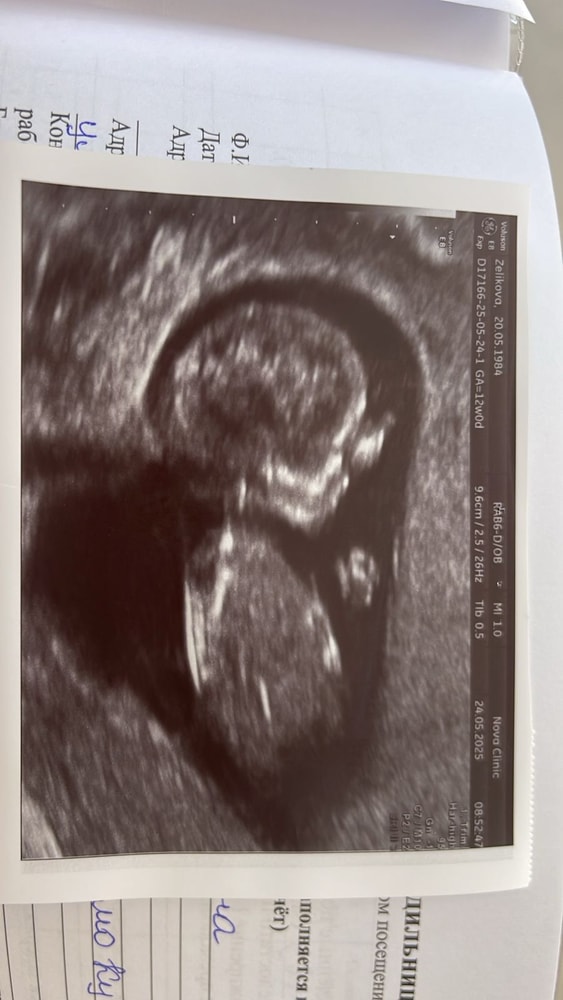

12 недель, 1 скрининг

На снимке малыш положил ладошку на глазки, наверное, думает: вот жеж мамааа! какая ты у меня тревожная! Успокойся уже, я с тобой, что ты переживаешь? Мне тут в животике у тебя тепло и уютно и никуда я не денусь до 40 неделек! Ты только корми меня вкусными фруктами-ягодками, овощами, мяском и молочком :)